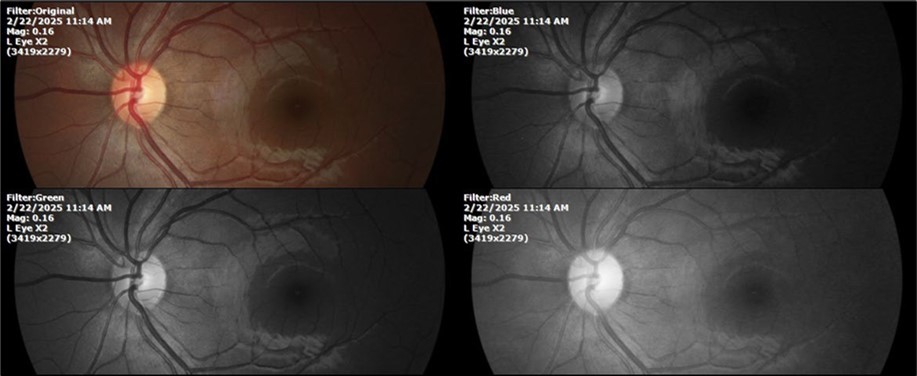

Figure 23.The mirror reflection of the left eye, without anomalies.

Figure 24.The eye that was not affected by the trauma (left side) remains in good condition.